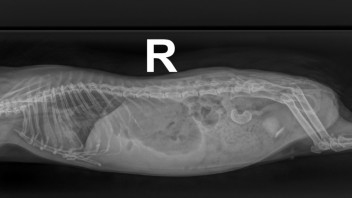

Die Heimtierärztin war heute nur im OP da, aber ich konnte Fienchen heute früh direkt zum Röntgen vorbeibringen und sie hat sich die Bilder kurz angeschaut und einen ersten Plan aufgestellt. Leider konnte ich nicht direkt mit ihr sprechen, aber morgen sollen wir wiederkommen, dann macht sie noch einen Ultraschall. Neben einer Aufgasung ist da nämlich noch eine Struktur im Bauchraum, die sie sich im Schall ansehen will.

Hat das von euch schon mal jemand gesehen? Könnte das die Blase und somit ein Stein sein? Und rechts unten davon auch was komisches(?)

• Rechts unten würde ich zur Blase zuordnen und deshalb auf Blasengries oder Blasenschlamm tippen. Das oben könnte evtl. ein riesiger Blasenstein sein.

Das ist bestimmt sehr schmerzhaft. Arme Maus! Ich drücke euch ganz sehr die Daumen! Das wird bestimmt operiert werden müssen. 😥